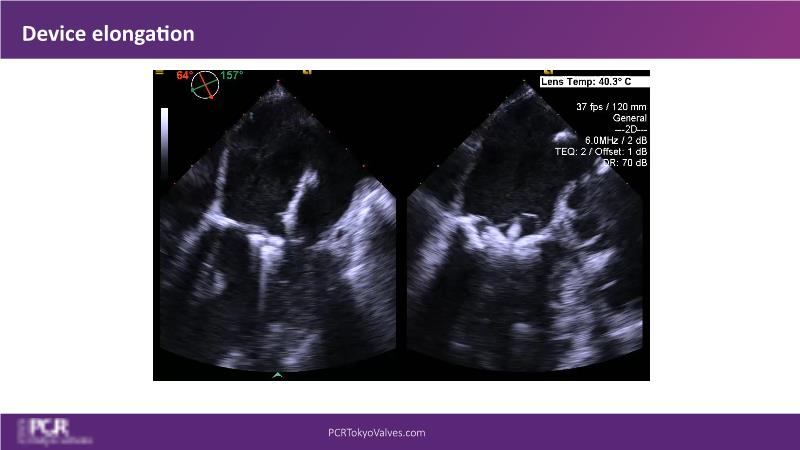

Watch this session to get an overview of a new TEER device, follow the step-by-step procedure related to initial experiences with this device for a Japanese patient with degenerative mitral regurgitation, learn about the latest data from RCT and registries, and follow discussions of challenging TEER cases!

- To learn procedural step-by-step of novel device